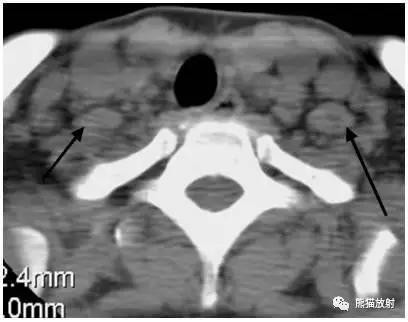

显示左侧Ⅲ区颈部淋巴结转移。

淋巴瘤。箭头显示右侧Ⅳ区,左侧Ⅴ区淋巴结增大。

淋巴瘤。黑箭显示双侧锁骨上窝淋巴结增大。